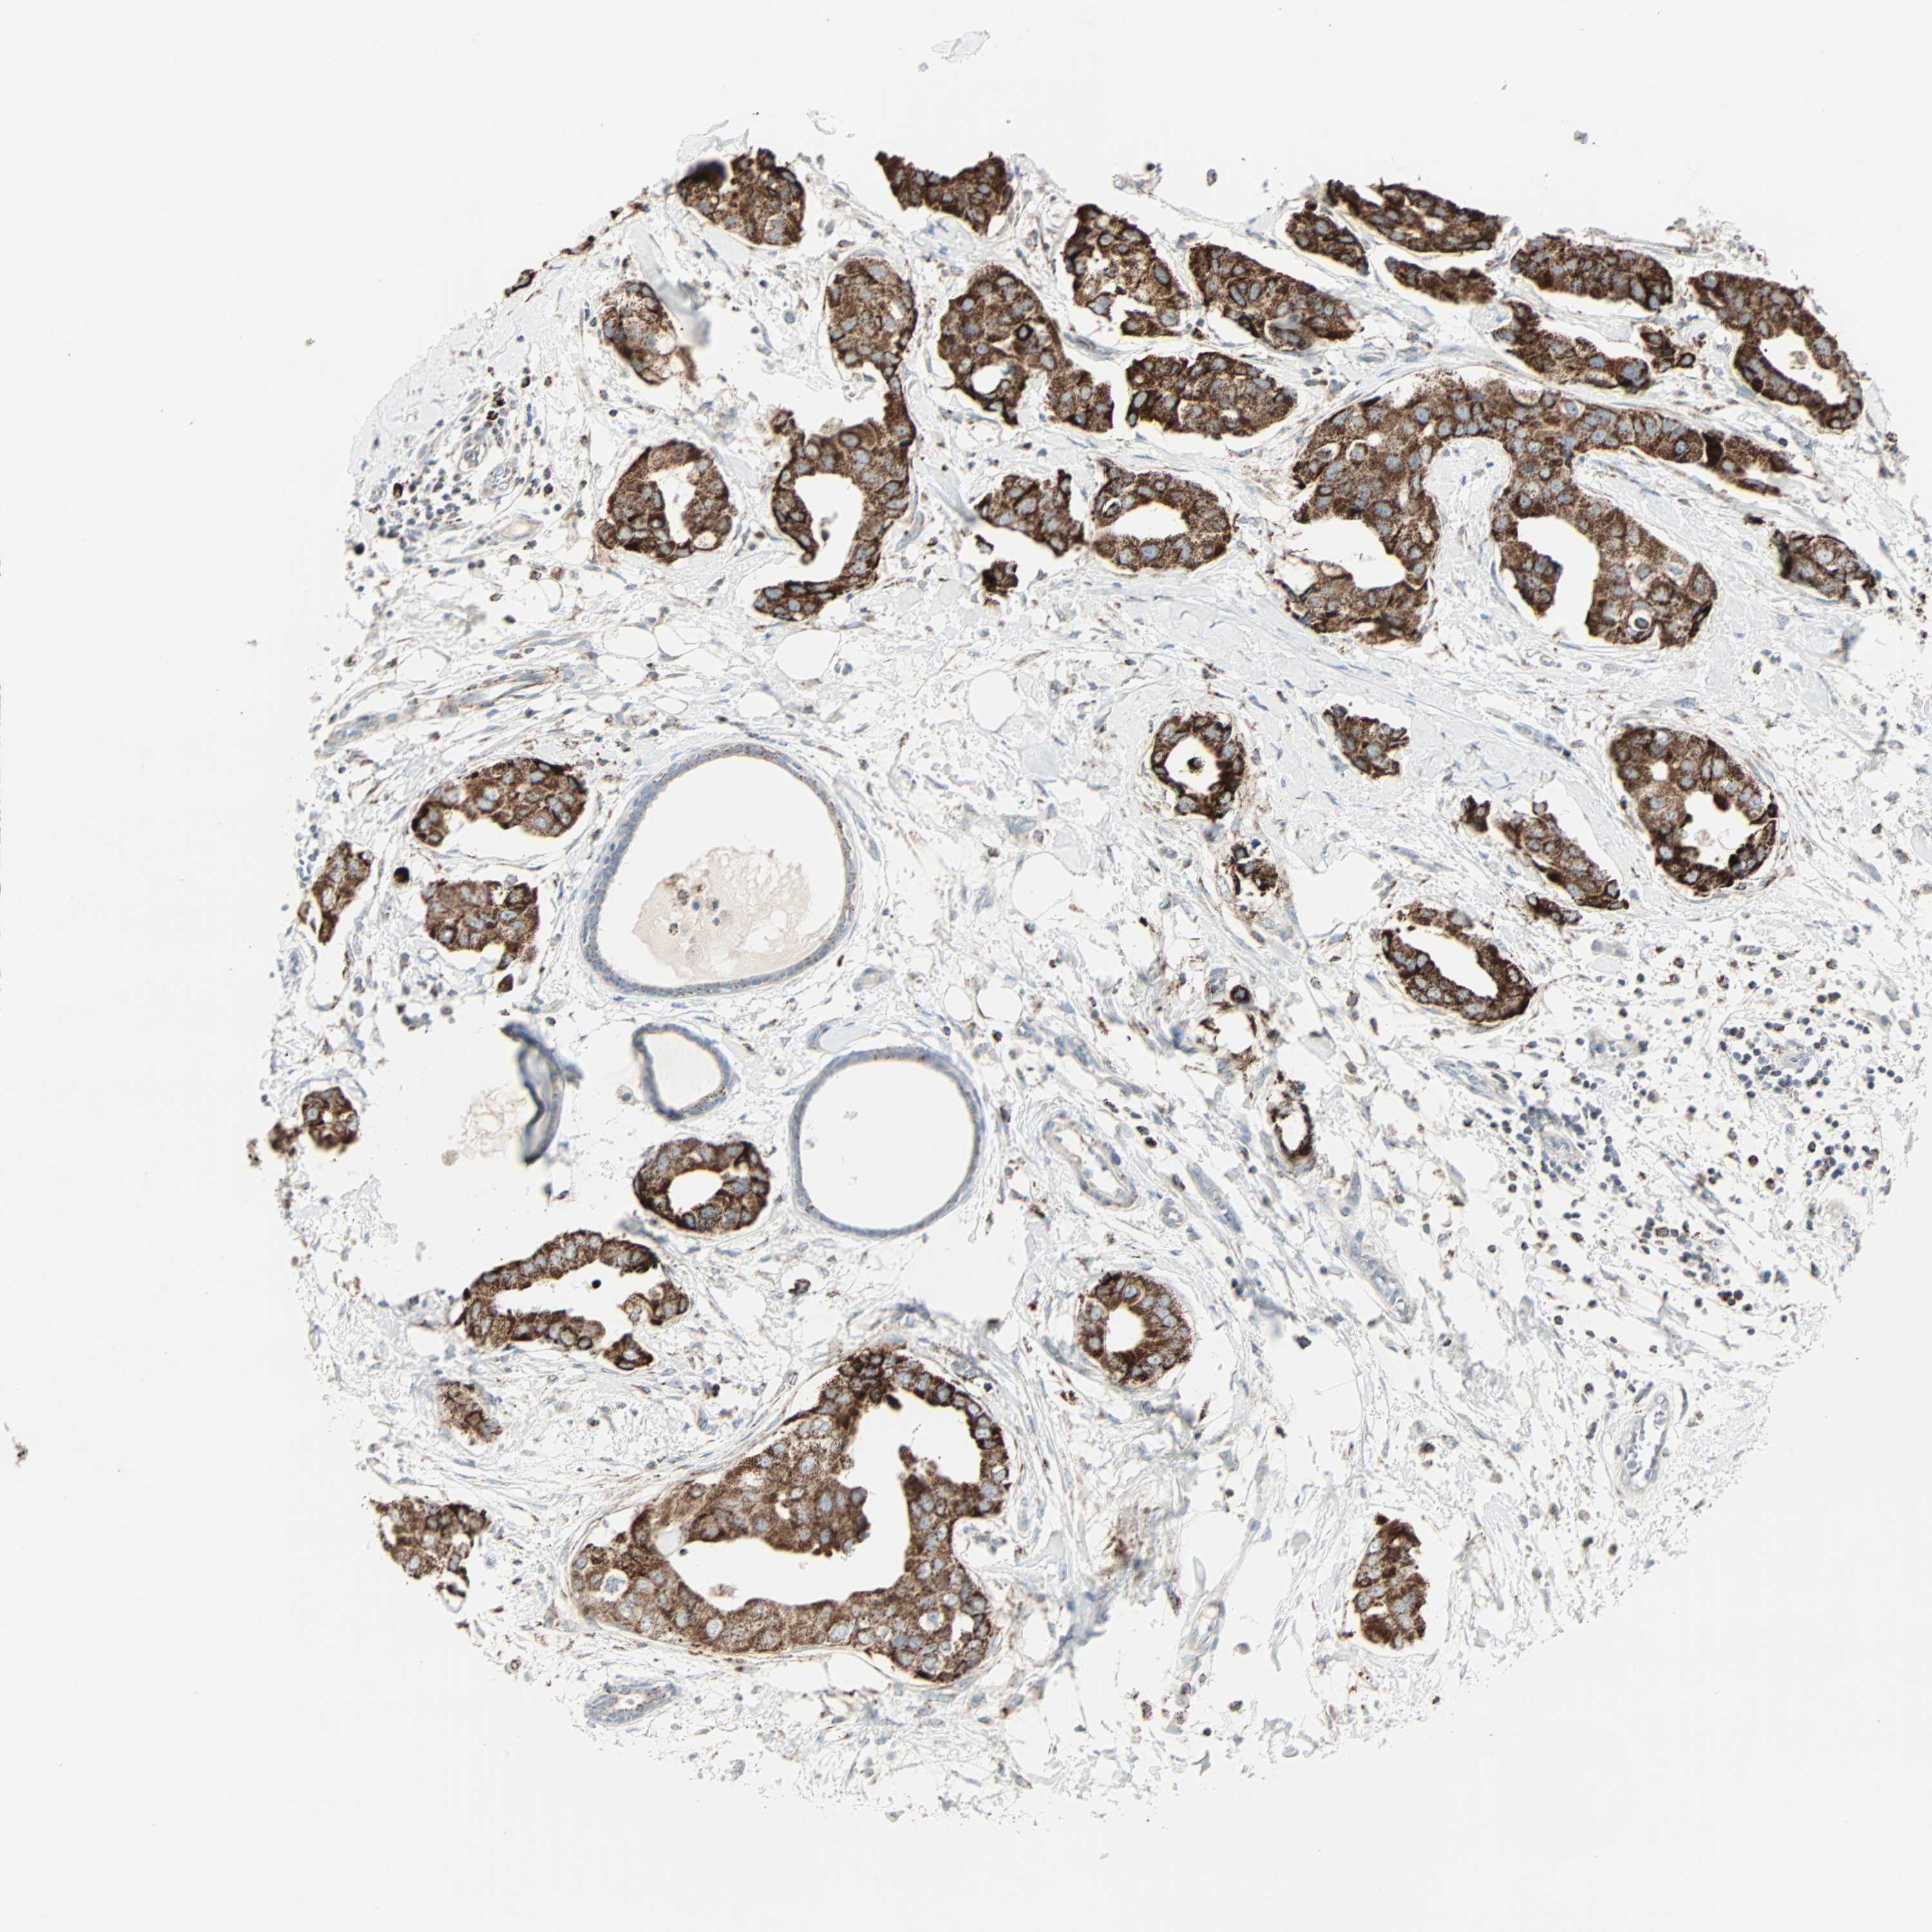

CANCER BREAST CANCER Show tissue menu

Breast cancer

Human cancer